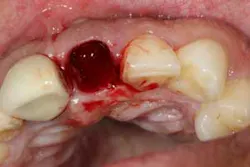

After removal of the tooth, there are many methods of debriding the socket and various instrumentation that one can use. This author chooses to use a spoon excavator or spoon curette with serrations as a means of performing mechanical debridement (figure 4). After mechanical debridement, copious saline is used to irrigate the socket (figure 5), followed by the placement of cotton pellets soaked with either tetracycline (50 mg/ml) or 60% citric acid into the socket. After chemical modification, the socket is again irrigated and flushed with saline.

Visual inspection of the socket postdebridement should show a clean alveolus with no evidence of fibrous tissue tags (figure 6). Although irrigation and decontamination are important, equally important is to ensure that the socket is not desiccated by these procedures. Studies have shown that poor bone healing and dry sockets have occurred postsocket irrigation if bleeding is not stimulated. (5) Decortication of the socket to initiate blood flow is recommended prior to bone grafting/socket closure to initiate osteoinduction/angiogenesis and clot formation (figure 7). By creating the right environment for bone healing and removing obstacles to maturation, your bone graft will appreciate your efforts and reward you with good integration and healing.